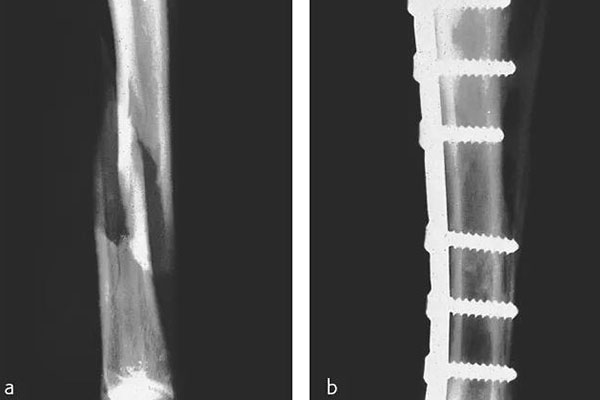

那在檢測的時候還需要看到植入物的情況,但由CFPEEK復(fù)合材料制成的零件通常具有放射透性,幾乎無法通過X射線檢測。就通過添加諸如鉭絲之類的X射線散射材料,可以使植入物變得可見。可以看下圖展示了一個固定骨折骨頭的骨愈合板。可以看出,通過設(shè)計已對放射密度進(jìn)行了定制,以便在盡量減少對骨折部位遮擋的同時可視化組件。重要的是,實現(xiàn)X射線可見性的同時也能保持清晰的MRI圖像。